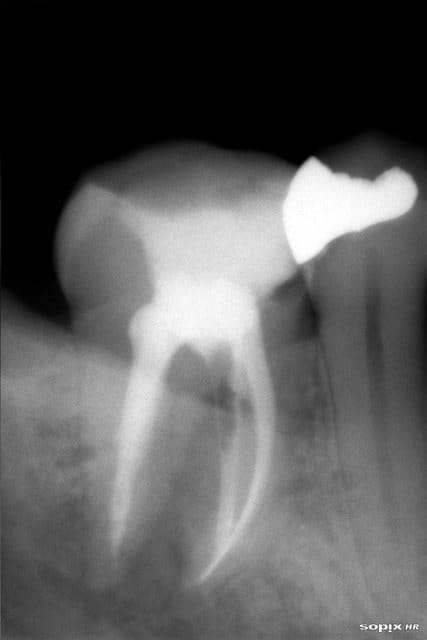

Une bonne serie d'endo molaires 4 canaux sur le même patient

Flodec : preparation aux Protapers et obturation monocone rouge 4% ou jaune 4% et guttacondensor avec Sealite, rien de bien incroyable

Chicot : c'est vrai que pour la 46 j'ai hesité à l'enlever, vu la mobilité, fistule, douleur mais je préfère toujours tenter

Flodec : je vais jusqu'au rouge jusqu'à ma LT... je ne bourre pas la pate au lentulo juste un peu au cone de papier puis gutta en general Isotaper 60pc à 4% condensation laterale puis gutta condensor et je foule au Machtou.

pour cette 46 pas d'interseance, le canal était bien sec à la fin de l'endo => donc obturation, séance 1h30 facilité car anesthesie sans problème et canaux très larges

RX à 8 mois, d'habitude je fais à 3 mois mais là pas possible pour le patient